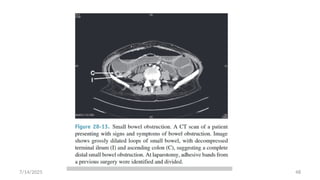

7/14/2025

Cont…

 CT scanning may also provide evidence for the

presence of closed loop obstruction and strangulation

 Closed-loop obstruction is suggested by the presence

of a

U-shaped or C-shaped dilated bowel loop associated with

a radial distribution of mesenteric vessels converging

toward a torsion point